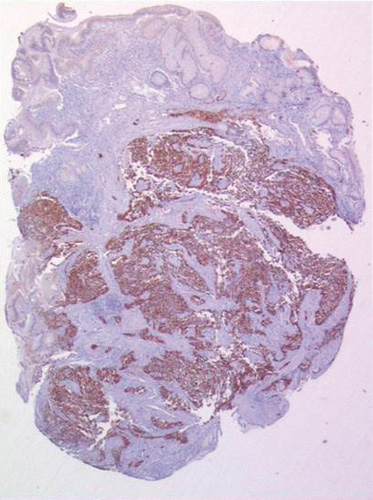

Les résultats d’une nouvelle étude publiée dans la revue Frontiers in Oncology suggèrent qu’une résection de la tumeur primitive (RTP) doit être proposée aux patients atteints d’un carcinome neuroendocrine gastrique (CNEG) avec métastases à distance, car elle permet d’améliorer la survie, comparativement à l’absence d’intervention chirurgicale.